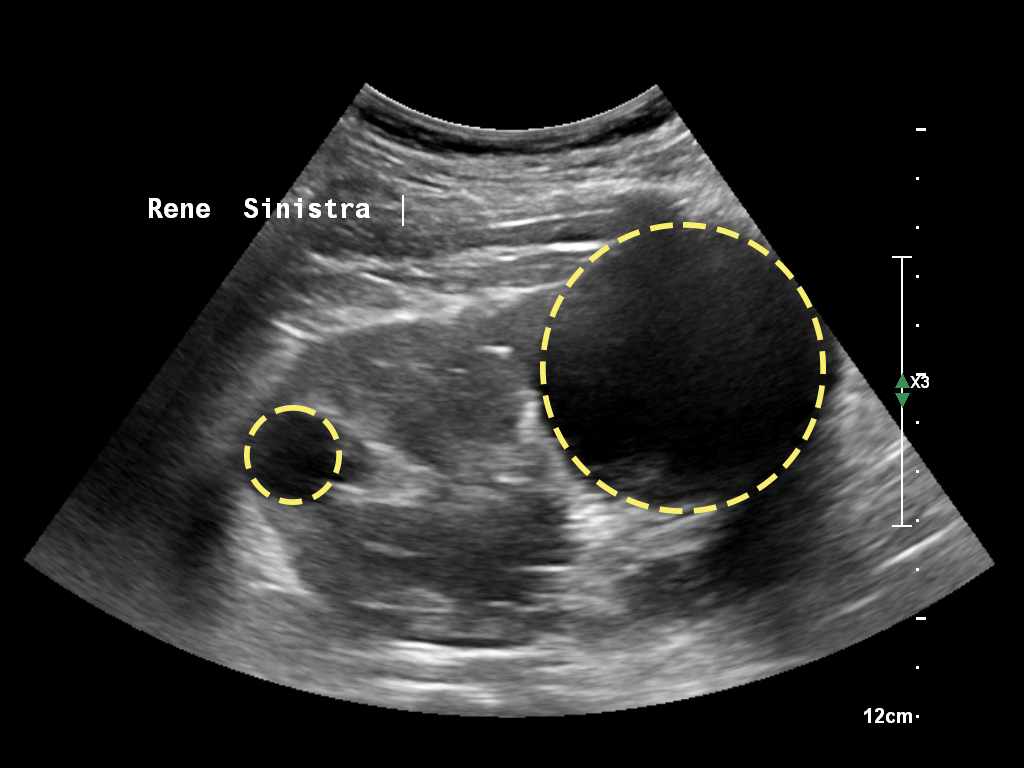

Anche in caso di cisti palpabili attraverso una visita medica (si parla di cisti di oltre 10 cm di diametro) la diagnosi può avvenire solo mediante la visualizzazione con immagini radiologiche. La più comune metodica utilizzata, e facilmente reperibile è l’ecografia dell’addome.

Nel caso di dubbi la valutazione può essere approfondita con TC o risonanza magnetica che aiutano a chiarire quadri, specialmente in caso di cisti complesse con componenti sospette molto piccole.